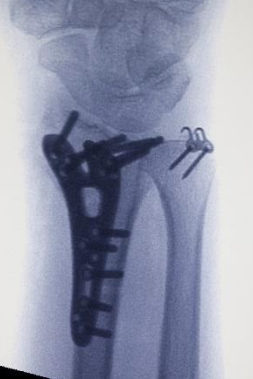

Konservatif tedavinin uygun olmadığı durumlarda cerrahi tespit önerilebilir. Distal radiusun sabitlenmesinde artık en yaygın yaklaşım, bileğin volar yönündendir. Bu, anatomik volar kilitleme plakasının kullanılmasını gerektirir. Birçok avantajı arasında daha az fark edilen bir cerrahi yara izi yer alır; kilitleme vidalı titanyum plaka daha iyi stabilite sağlar ve özellikle osteoporotik kemikleri olan hastalar için endikedir. Ulnar stiloid tabanda kırılmışsa kırığın onarılması tavsiye edilir.

Cerrahlar, kemik iyileşirken kırık kemiği doğru pozisyonda tutmak için birkaç alternatife sahiptir :